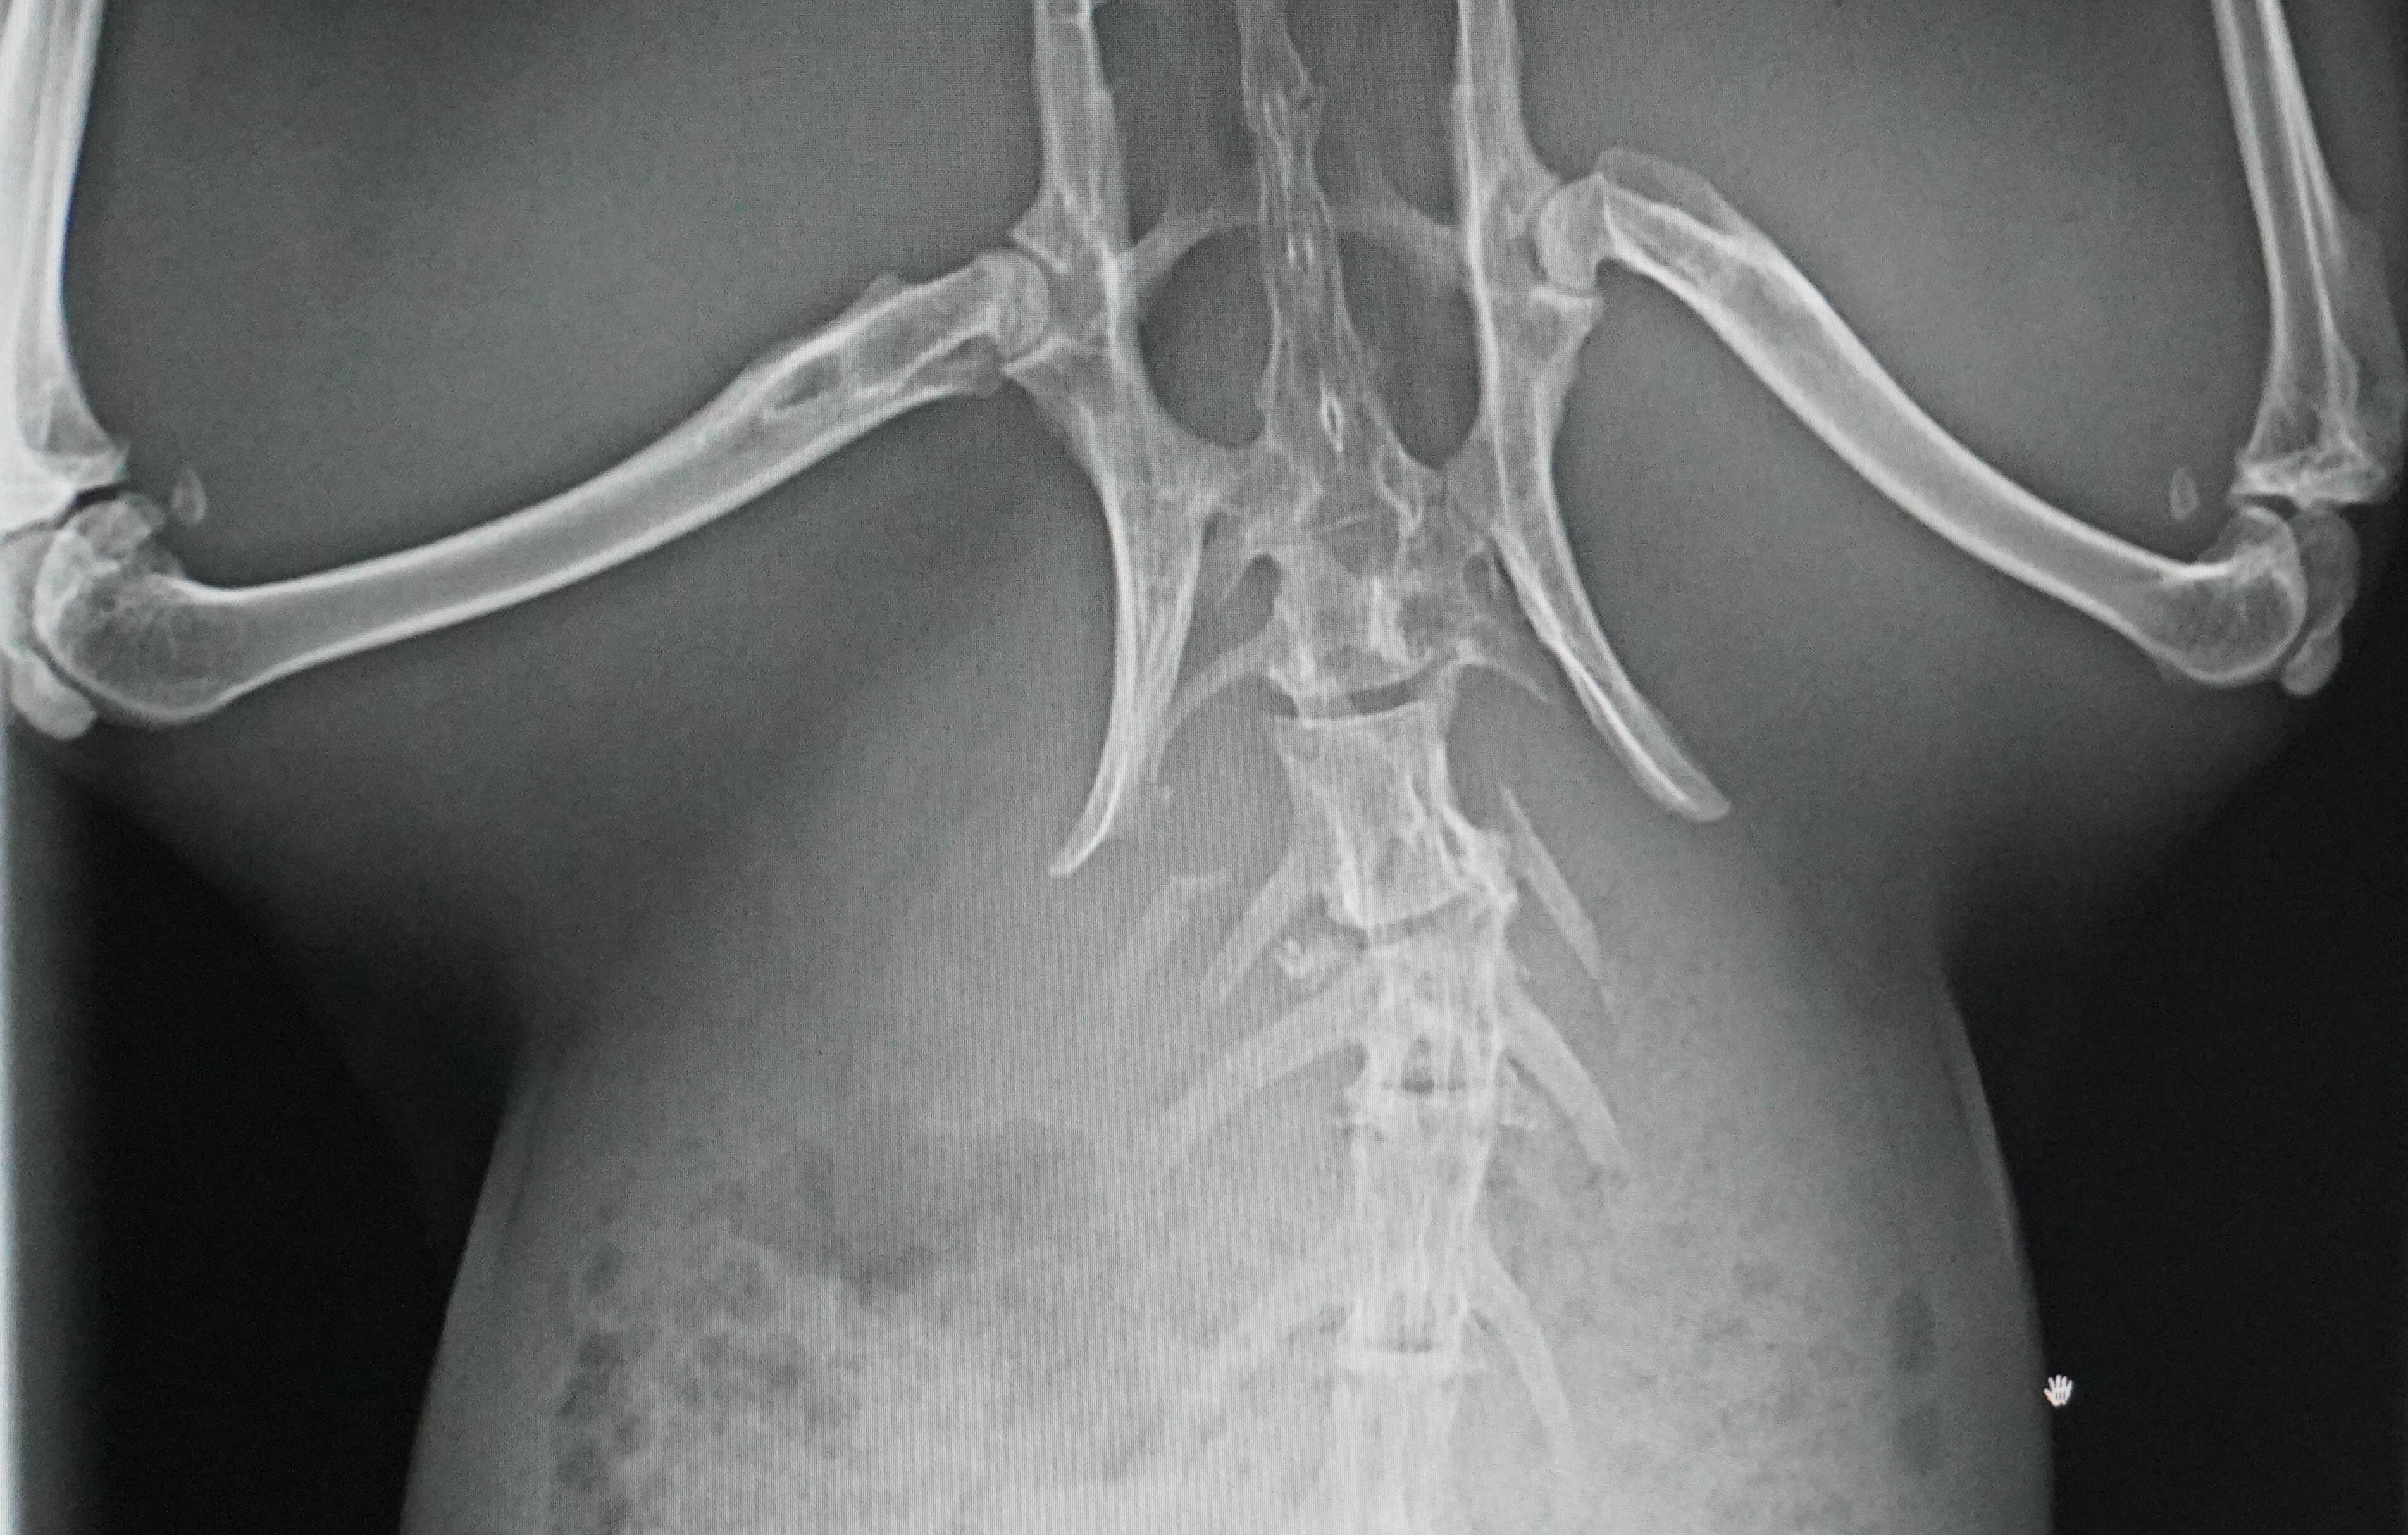

相変わらず、折れた腕は痛そうにしています。